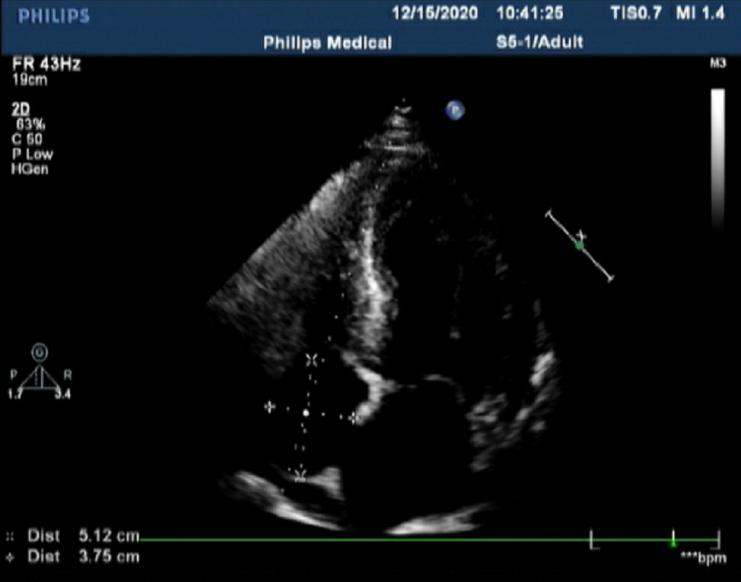

图2.心脏彩超左室壁均匀性增厚

2月前,一名50岁男性患者因反复活动后气促半年,加重2月来到心内二科住院,患者爬楼或快步行走时即感气促,伴胸闷,休息后缓解,无胸痛、心悸、黑朦、晕厥。2月前上述症状较前加重,活动耐量下降,无夜间阵发性呼吸困难。2017年诊断“重度阻塞性睡眠呼吸暂停低通气综合征”,使用无创呼吸机治疗。有猝死家族史,其父亲及兄弟姐妹中3人于50岁左右猝死。入院查NT-proBNP 2761.02 pg/ml↑,余住院患者常规实验室检验指标未见异常。心脏彩超双房增大,心肌弥漫性增厚并室壁运动幅度广泛减弱(室间隔15mm、左室后壁17mm),心功能参数减低LVEF 41%(辛普森法),少量心包积液。而心电图肢体导联及左胸壁导联QRS波低电压,这与肥厚型心肌病常伴心电图高电压的特征不匹配。